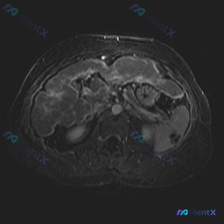

整理了一份很有意思的腹部影像病例,从单一病灶到全局判断,中间的思维路径值得复盘: --- 影像基础信息 - 序列:腹部MRI T2加权成像(T2WI)轴位 - 背景脂肪信号未抑制,为标准T2WI 关键影像表现 1. 脾脏病灶: - 位置:脾脏边缘(外侧) - 数量:2个类圆形结节 - 信号:T2WI...

今天看到一个聚焦「脾脏病变」的读片资料,整理了一下思路,觉得挺有讨论意义的——尤其是当「临床预设」和「手头影像事实」不一致的时候。 --- 先把影像信息摆出来 这是一张腹部MRI轴位T2加权图像,客观所见如下: - 肝脏:信号大致均匀,包膜光滑,肝内胆管无扩张,未见明确高低信号结节; - 脾脏:划重...

今天看到一张挺有意思的腹部MRI-T2轴位图像,临床初步疑问是“脾脏病变”,但仔细看完觉得思路需要扭转一下,整理出来和大家讨论。 先把影像里的关键信息捋一遍: - 序列与质量:T2WI,液体(胆汁、胃液、腹水)呈高信号;有明显呼吸运动伪影,前壁和部分器官边缘模糊,细节观察受一定影响。 - 大家关注的...